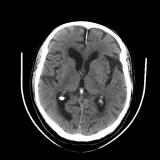

Over 2,100 interactive radiology cases, curated by radiologists for your level of training. Scroll, window, and view cases full screen — just like on PACS. Click linked findings in each writeup to jump straight to them on the image. Cases include sample reports, a focused discussion section, original illustrations, and videos.

Neuro Fellowship — a course tailored for fellows and practicing radiologists with in-depth reviews of advanced neuro topics like brain tumors, featuring rare diagnoses, differentials, and clinical pearls.

Casos totalmente interativos com as ferramentas que você espera em um PACS — rolagem, ajuste de janela, zoom, movimentação, medidas, ROIs e modo de tela cheia.

Anotações detalhadas destacam os achados principais diretamente nos casos. Clique nos achados vinculados nas descrições dos casos para ir ao local exato no exame.